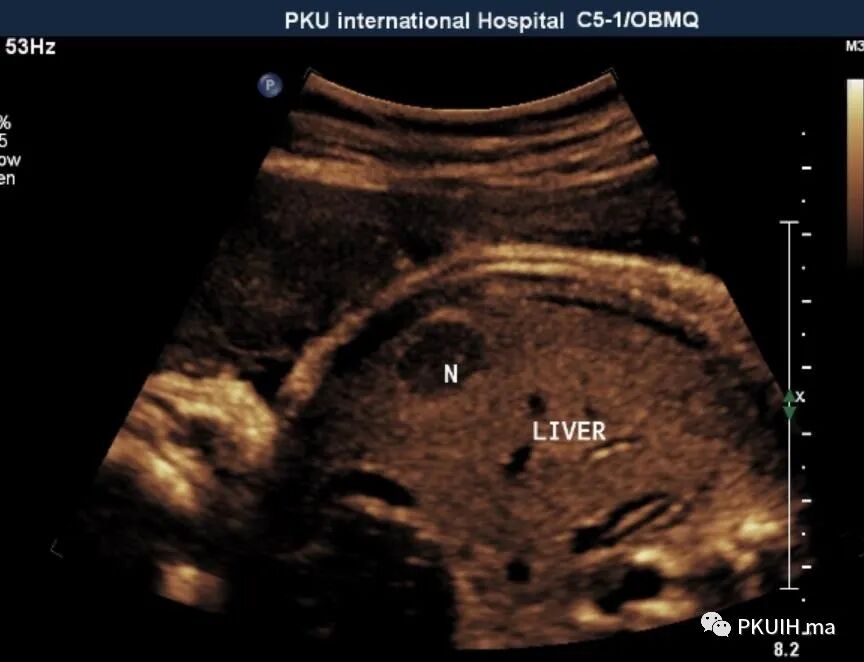

胎儿右肝内见一大小约1.4cm的实性低回声结节,边界清,形态规则,内回声均匀

胎儿期肝脏占位很少见,超声能发现的更少见。胎儿肝脏最常见的良性肿瘤是血管瘤、其次是错构瘤,恶性肿瘤是肝母细胞瘤。肝血管瘤较小时表现实性低回声,边界清或尚清,内回声均匀,较大时多成囊实性,内回声不均,部分可呈蜂窝样,边界多不清晰。CDFI:小的肿瘤血流不明显,大的肿瘤血流丰富。诊断主要依靠超声或MRI,但胎儿期对于小的肿瘤往往容易漏诊,尤其是晚孕期才出现的肿瘤。